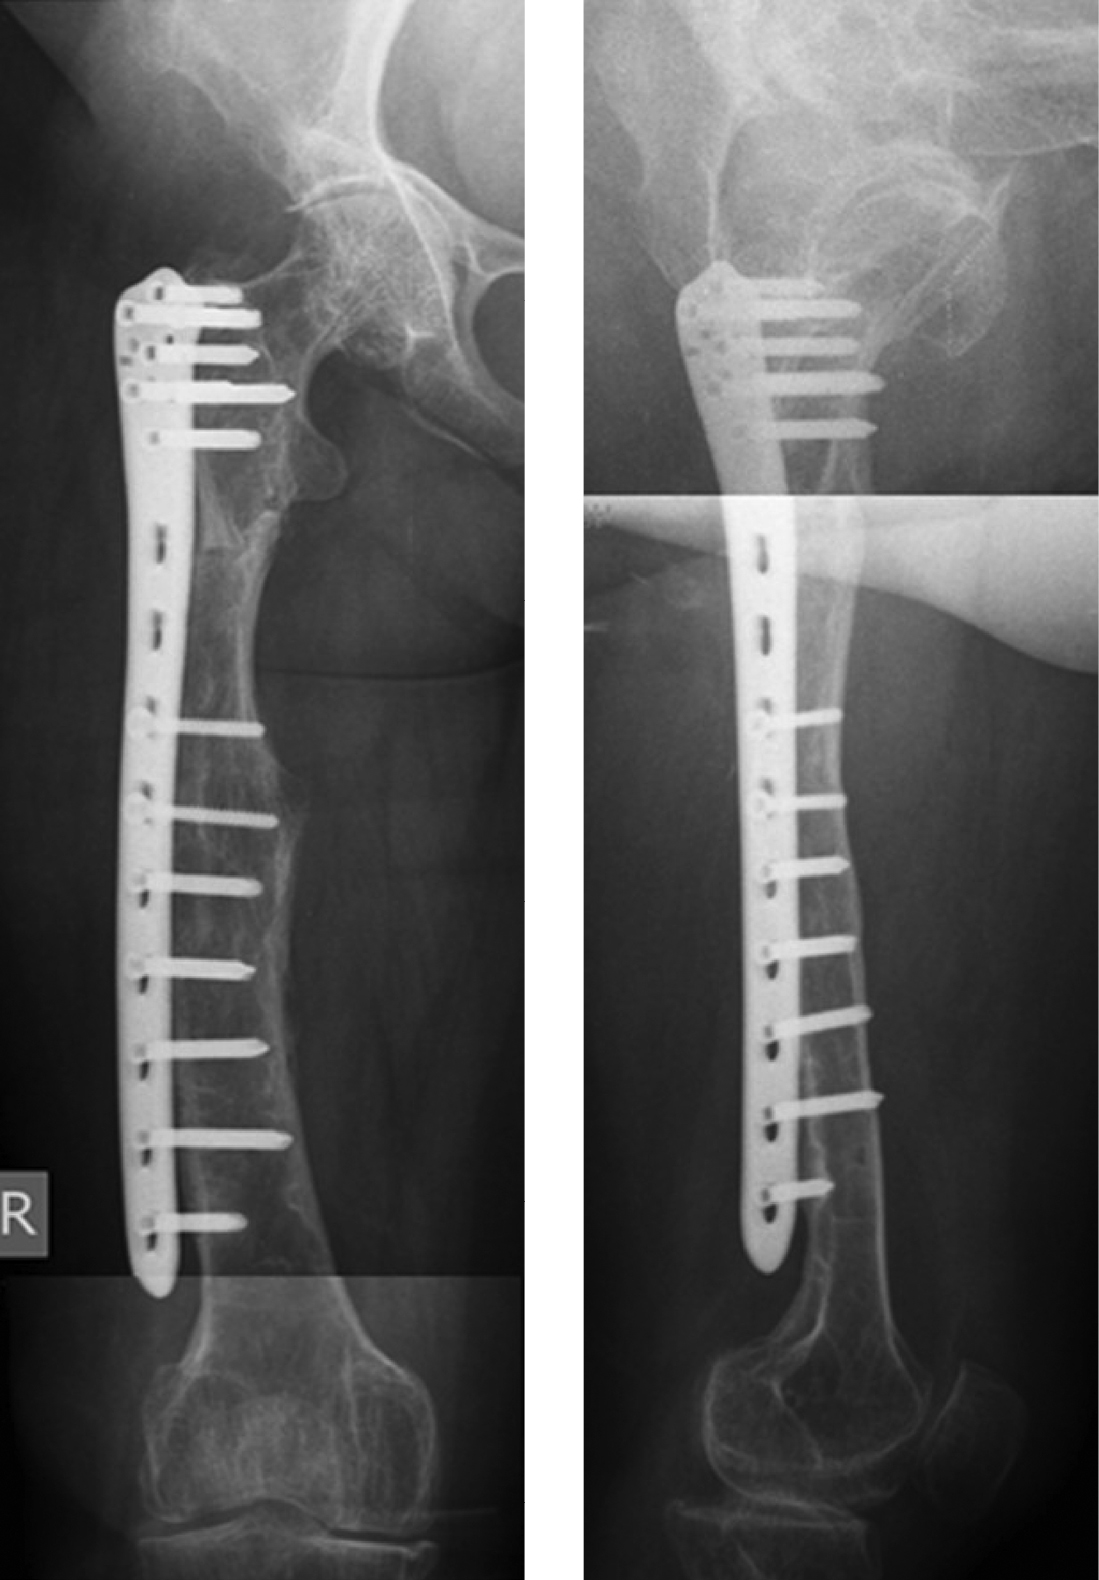

Рисунок 2. Рентгенограммы пациентки после остеосинтеза бедренной кости, блокируемой пластиной.

Во время этого вмешательства были выполнены открытая репозиция отломков с сохранением предсуществующей формы правой бедренной кости и компрессионный остеосинтез пластиной с блокированием. Для деконцентрации напряжения по краям фиксатора в надмыщелковой зоне бедренной кости использован неблокируемый бикортикальный винт 4,5 мм, а в проксимальном отделе блокируемый винт был введен по касательной, кпереди от дуги Адамса. Удаление имплантатов не планировалось. После консолидации кости на этом уровне в сроки 10 месяцев у пациентки восстановилась опороспособность конечности. Однако произошел периимплантный низкоэнергетический подвертельный перелом бедренной кости при падении на правый бок 01.01.2019 г.

В связи с этим после стационарного обследования 29 января 2019 г. была выполнена операция — удаление винтов и пластины из правого бедра, экономная адаптирующая резекция на уровне периимплантного перелома, корригирующая деваризация и компрессионный остеосинтез блокируемой пластиной. Для остеосинтеза использовалась «перевернутая» контрлатеральная дистальная бедренная пластина в режиме динамической компрессии двумя кортикальными винтами. Для деконцентрации напряжения был использован монокортикальный дистальный винт. С учетом сниженной минеральной плотности кости количество винтов, введенных в каждый отломок, было больше, чем при остеосинтезе бедренной кости без остеопороза (рис. 4).

Рисунок 4. Рентгенограммы пациентки после операции удаления имплантатов, корригирующей остеотомии проксимального отдела правой бедренной кости и остеосинтеза блокируемой пластиной.